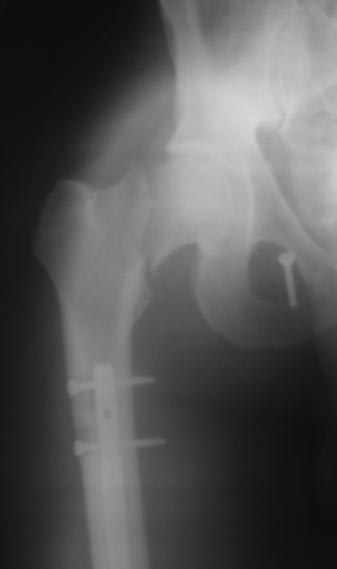

[Ortho] НЕСОСТОЯТЕЛЬНЫЙ ОСТЕОСИНТЕЗ ТАЗА

Представляю материалы по больному на сегодня. Сделали 13.03.2013г.

Имя     : Шеи?ка - прямои? 13.03.2013.JPG